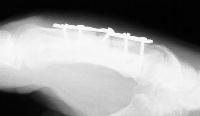

The injury: point blank handgun injury, palmar to dorsal through the middle metacarpal. Contusion of the third web space common digital nerve.

The treating surgeon debrided the wound and maintained length with intermetacarpal pins. When the wound was stable, the fracture was treated with bone graft, plate and screws.